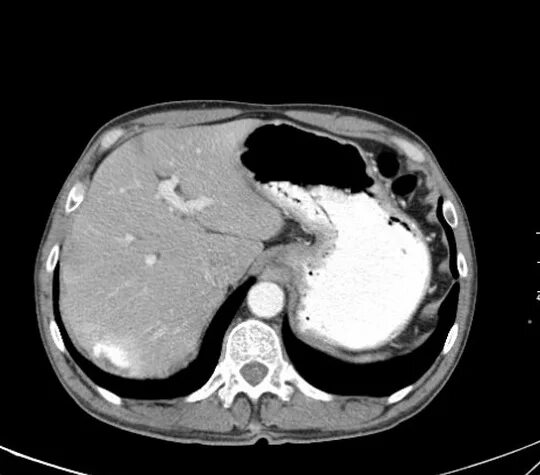

Образования печени кт